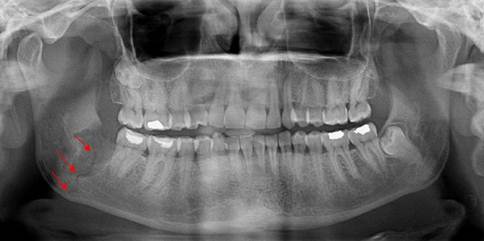

A 35-year-old female patient was admitted to the Department of Oral Surgery, Faculty of Dentistry, Istanbul University, with the complaint of mild pain in the right mandibular angle. She was systemically healthy and showed no swelling on the right side of the mandible due to infection. A panoramic radiograph revealed the presence of a mesioangular and deeply impacted mandibular right third molar surrounded by mild radiolucency. Extraction of the tooth was planned due to the pain and the radiolucency surrounding the crown and apex (Fig. 1).

Preoperative x-ray of the patient showing deeply impacted right third molar and radiolucency surrounding the tooth.